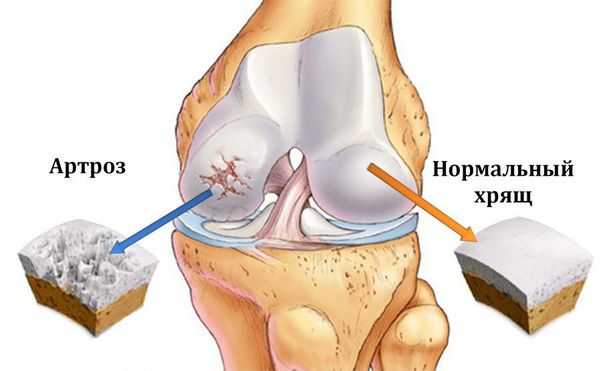

Первое существенное изменение при остеоартрозе – смягчение и образование ямок на гладкой поверхности хряща. По мере прогрессирования артрита слой хряща, покрывающий суставные поверхности, становится все тоньше, вплоть до полного разрушения, оставляя незащищенными концы костей.

Без нормальной скользящей поверхности становится болезненным и трудным двигать суставом. Поскольку хрящ продолжает разрушаться, по краям сустава формируются костные выросты, как бы компенсирующие потерю хряща за счет увеличения суставных поверхностей. Это является причиной деформаций суставов (сустав теряет свою форму) при артрите. В народе подобное состояние называют "отложение солей", что является просто неграмотным названием артроза.